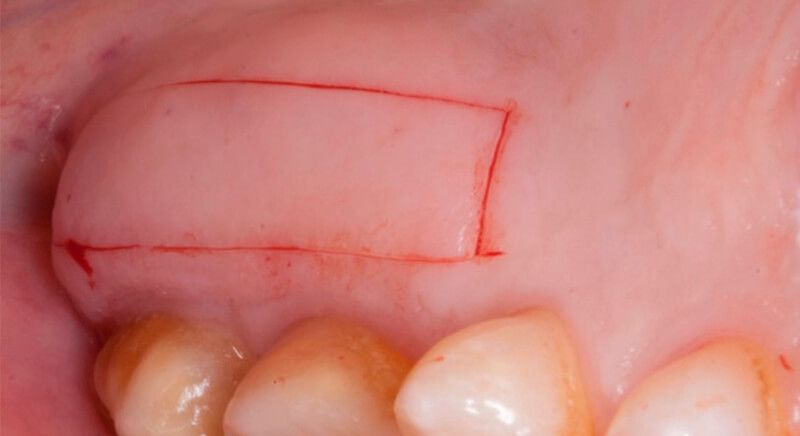

The socket was filled with a xenograft after the extraction and a graft of connective tissue was placed in the vestibular area of the two upper central incisors.

The tissue with epithelium was taken from the palate and de-epithelialized outside of the mouth. This obtains a lamina propria graft with better density and quality than if it were obtained with a single incision to the palate.